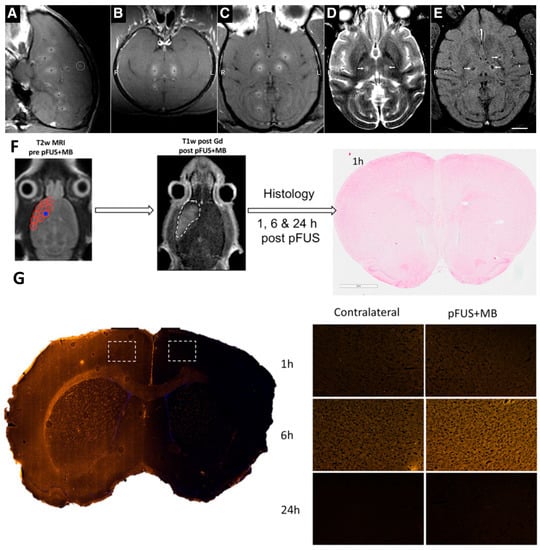

- Kovacs, Z.I.; Kim, S.; Jikaria, N.; Qureshi, F.; Milo, B.; Lewis, B.K.; Bresler, M.; Burks, S.R.; Frank, J.A. Disrupting the blood-brain barrier by focused ultrasound induces sterile inflammation. Proc. Natl. Acad. Sci. USA 2017, 114, E75–E84. [Google Scholar] [CrossRef]